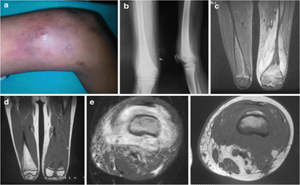

PubMed Central: Published on 2020 August AHOM was defined as any bone infection with a period between symptoms onset and diagnosis < two weeks. AHOM was defined complicated in the presence of sepsis, septic shock, arthritis, cellulitis, sub-periosteal or muscle abscess, deep vein thrombosis pathological fracture, septic emboli or hosp...